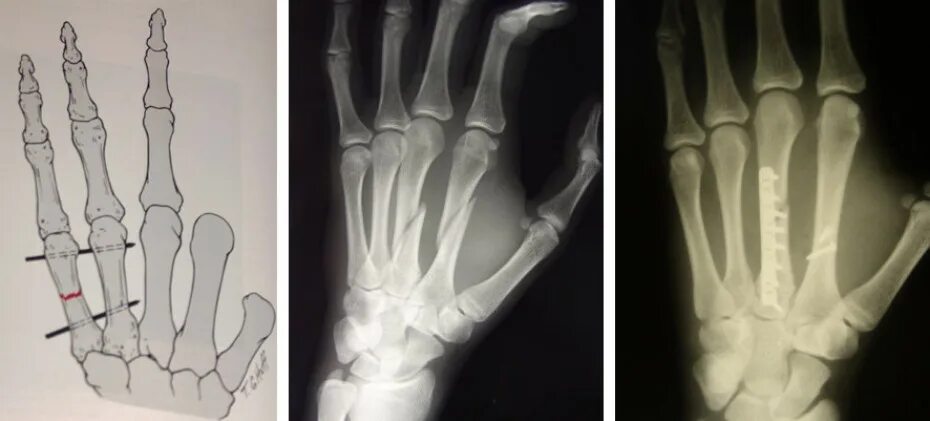

Спицы при переломе 5 пястной кости. спица при переломе пястной кости кисти. остеосинтез пястной кости спицами. остеосинтез пятой пястной кости кисти.

Остеосинтез спицей перелом пястной кости. остеосинтез 2 пястной кости спицами. остеосинтез пястной кисти. перелом беннета остеосинтез.

Остеосинтез пястной кости спицами. перелом пястной кости спицы. перелом 3 пястной кости левой руки.

Остеосинтез 2 пястной кости. остеосинтез 5 пястной кости. остеосинтез 5 пястной кости кисти спицей. остеосинтез пястной кости спицами.

Остеосинтез пястных костей спицами. остеосинтез 5 пястной кости спицей киршнера. спицы при переломе 5 пястной кости. остеосинтез пястной кости спицами.

Спицы в первой пястной кости. спицы при переломе пястных костей. спицы при переломе пястной кости.

Спицы киршнера перелом руки. остеосинтез пястной кости спицей киршнера. остеосинтез пястной кости спицами. остеосинтез пястных костей спицами киршнера.